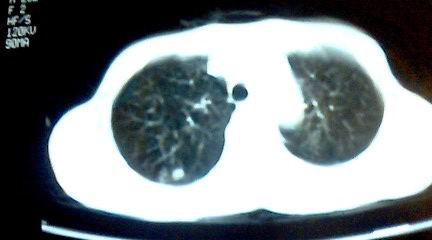

标题: CT25218:请教!胸部CT,胸8椎体骨质破坏,伴周围软组织肿。 [打印本页]

标题: CT25218:请教!胸部CT,胸8椎体骨质破坏,伴周围软组织肿。

患者,女41岁,肢体乏力。

双肺及胸椎结核。

双肺及胸椎结核。支持!

两肺上叶继发性肺结核;胸椎结核并椎旁寒性脓肿形成。